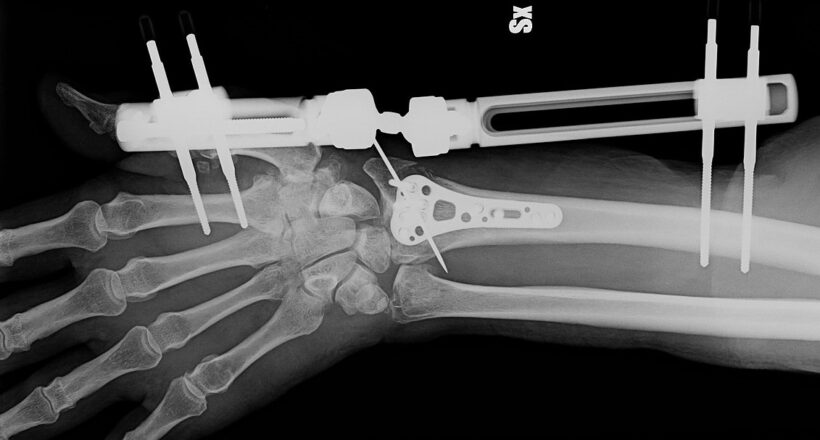

La formule de Bone-02 combine des composés du calcium et des protéines particulières, assurant une liaison à la fois solide, flexible et sûre. Des essais cliniques menés avec succès sur plus de 150 patients ont démontré une résistance à la traction (supérieure à 1,78 kN), au cisaillement (0,5 MPa), et à la compression (proche de 10 MPa) – des performances qui suggèrent que cette colle pourrait remplacer les implants métalliques traditionnels utilisés dans les fractures complexes.

Son application ne nécessite qu’une incision minimale et la colle est directement appliquée dans la zone fracturée, scellant les fragments osseux en quelques minutes. De plus, la colle Bone-02 est biodégradable et se résorbe naturellement au fur et à mesure que la structure osseuse se régénère, évitant ainsi une seconde opération pour retirer des plaques ou des vis. Cette propriété réduit donc les risques d’infection de manière considérable ainsi que la durée de convalescence.